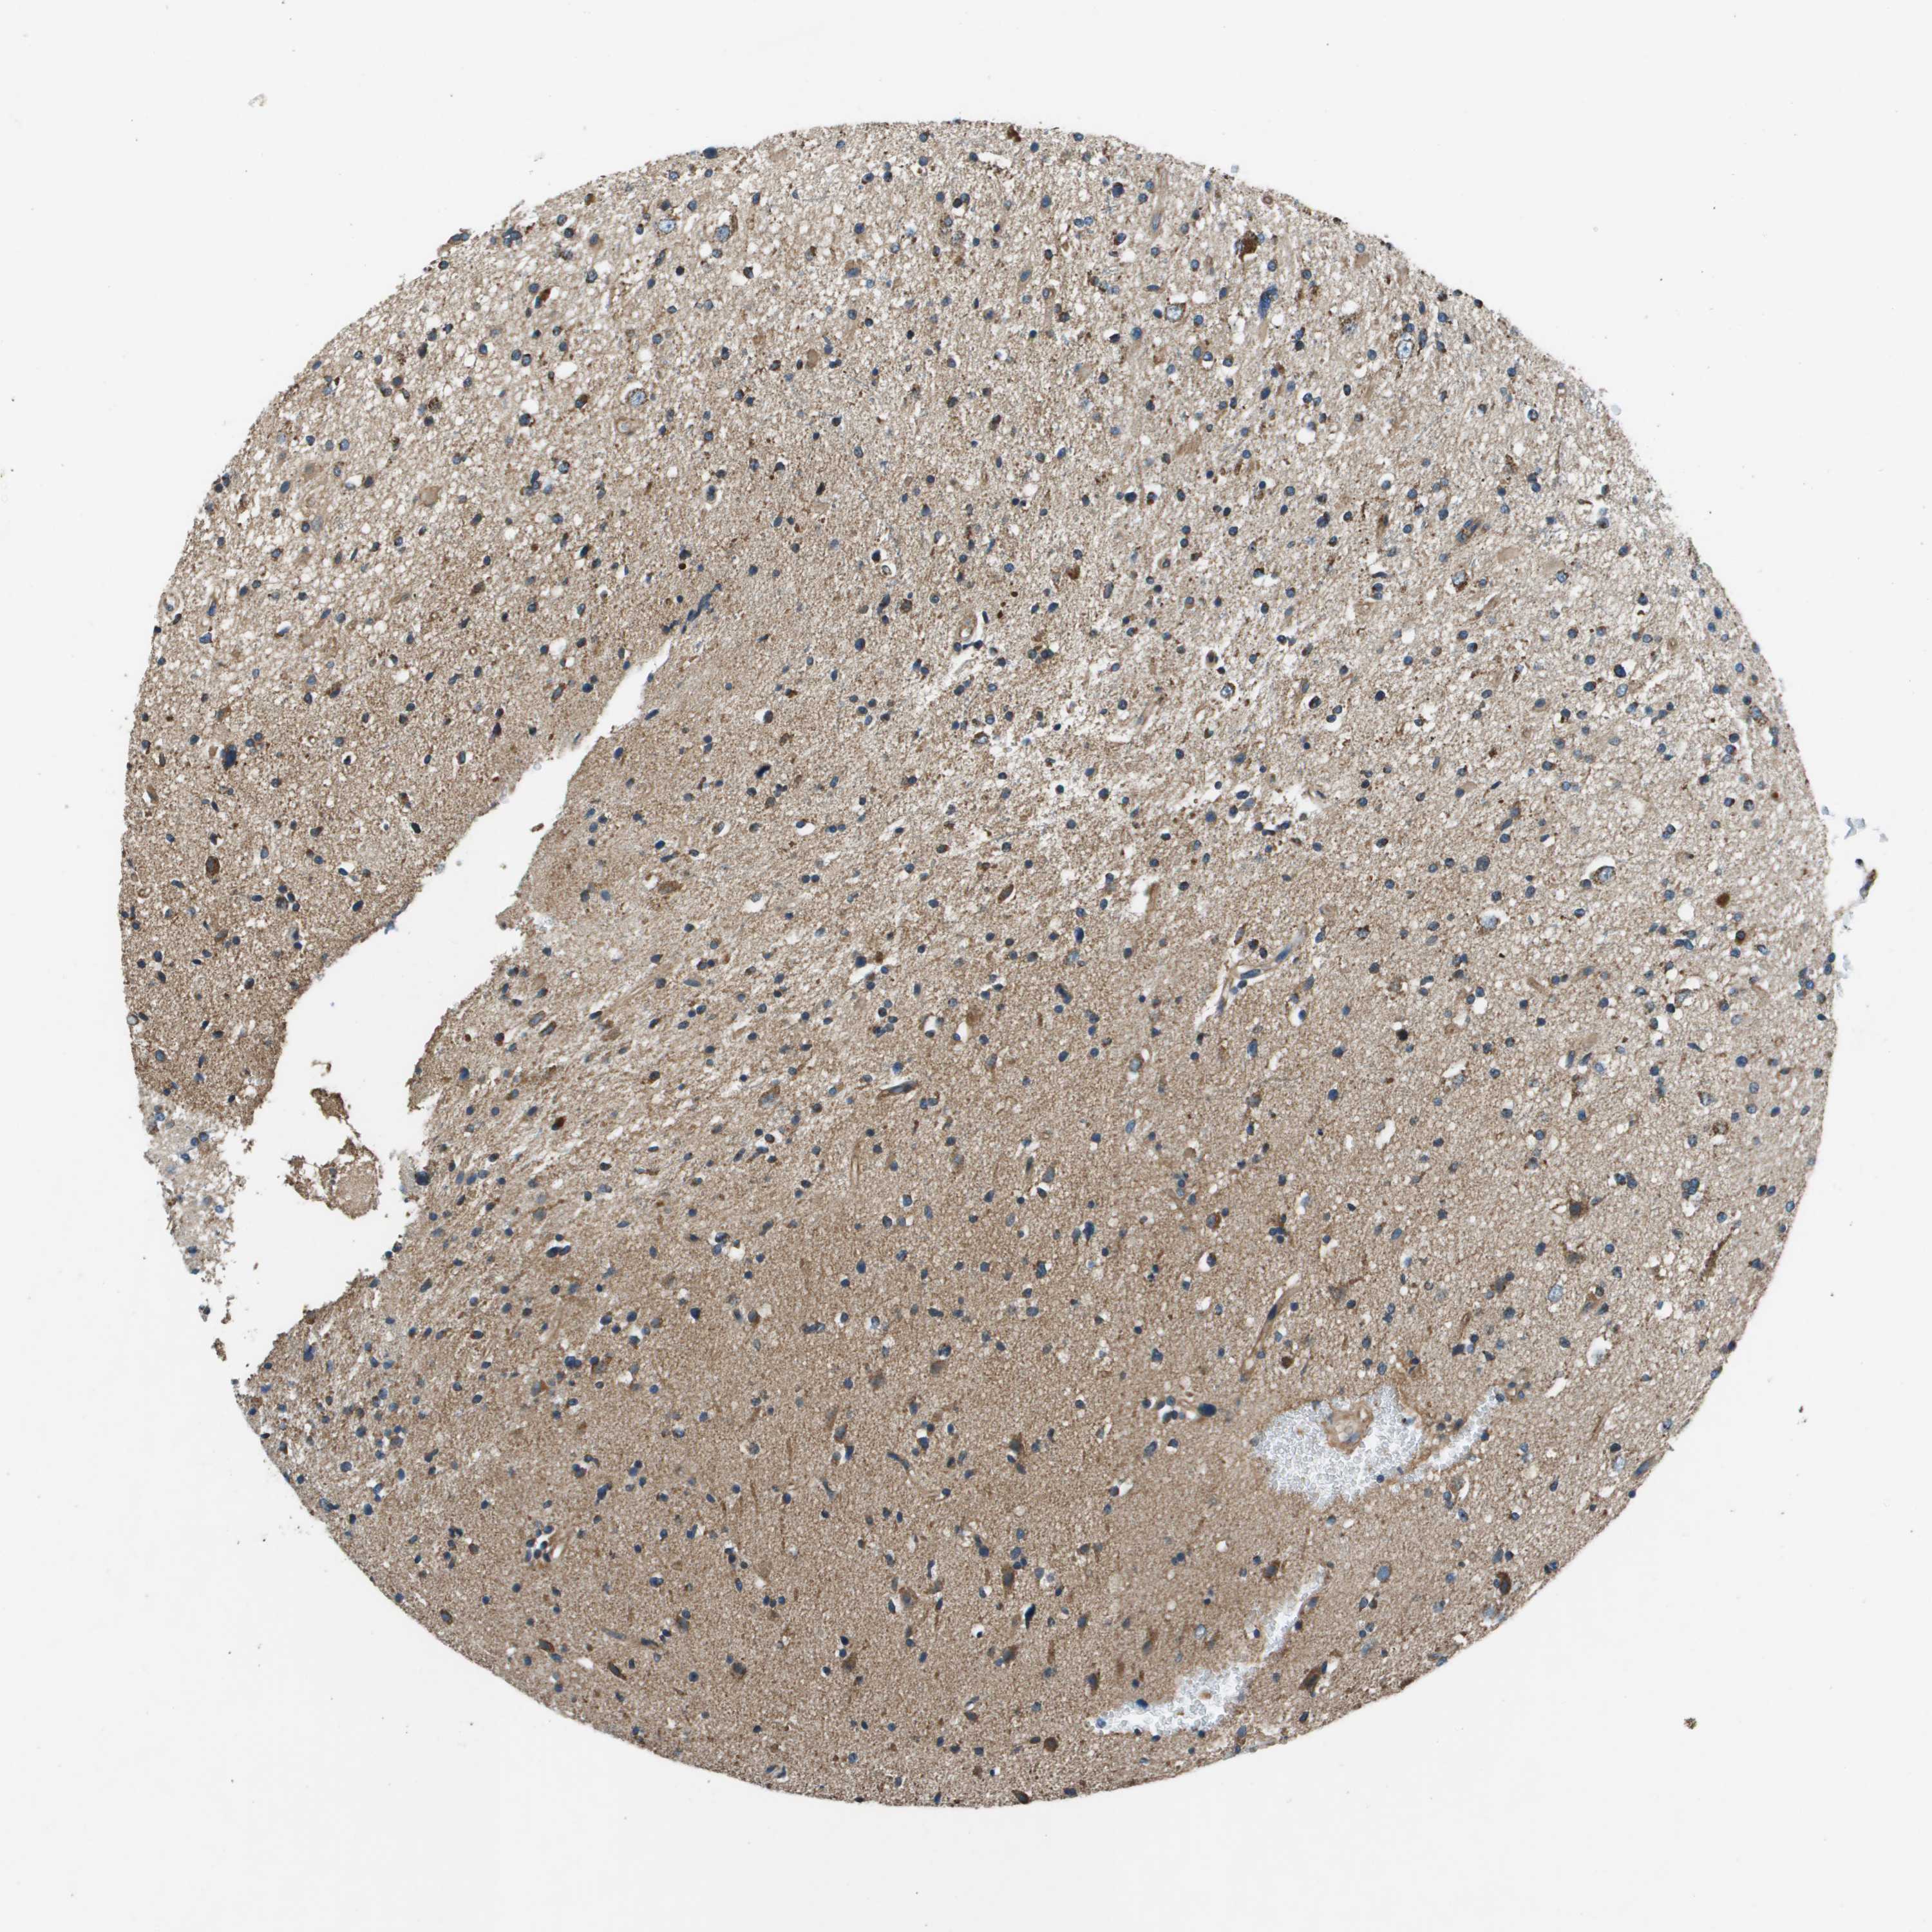

GLIOMA - Protein expressioni

A mouse-over function shows sample information and annotation data. Click on an image to view it in a full screen mode. Samples can be filtered based on level of antibody staining by selecting one or several of the following categories: high, medium, low and not detected. The assay and annotation is described here.

Note that samples used for immunohistochemistry by the Human Protein Atlas do not correspond to samples in the TCGA dataset.

Antibody stainingi

Antibody staining in the annotated cell types in the current human tissue is reported as not detected, low, medium, or high, based on conventional immunohistochemistry profiling in selected tissues. This score is based on the combination of the staining intensity and fraction of stained cells.

Each image is clickable and will lead to virtual microscopy that enables deeper exploration of all samples and also displays staining intensity scores, fraction scores and subcellular localization as well as patient and tissue information for each sample.

Antibody HPA014547

Staining

High

Medium

Low

Not detected

Intensity

Strong

Moderate

Weak

Negative

Quantity

>75%

75%-25%

<25%

None

Location

Nuclear

Cytoplasmic/membranous

Cytoplasmic/membranous,nuclear

Glioma, malignant, High grade

Glioma, malignant, Low grade